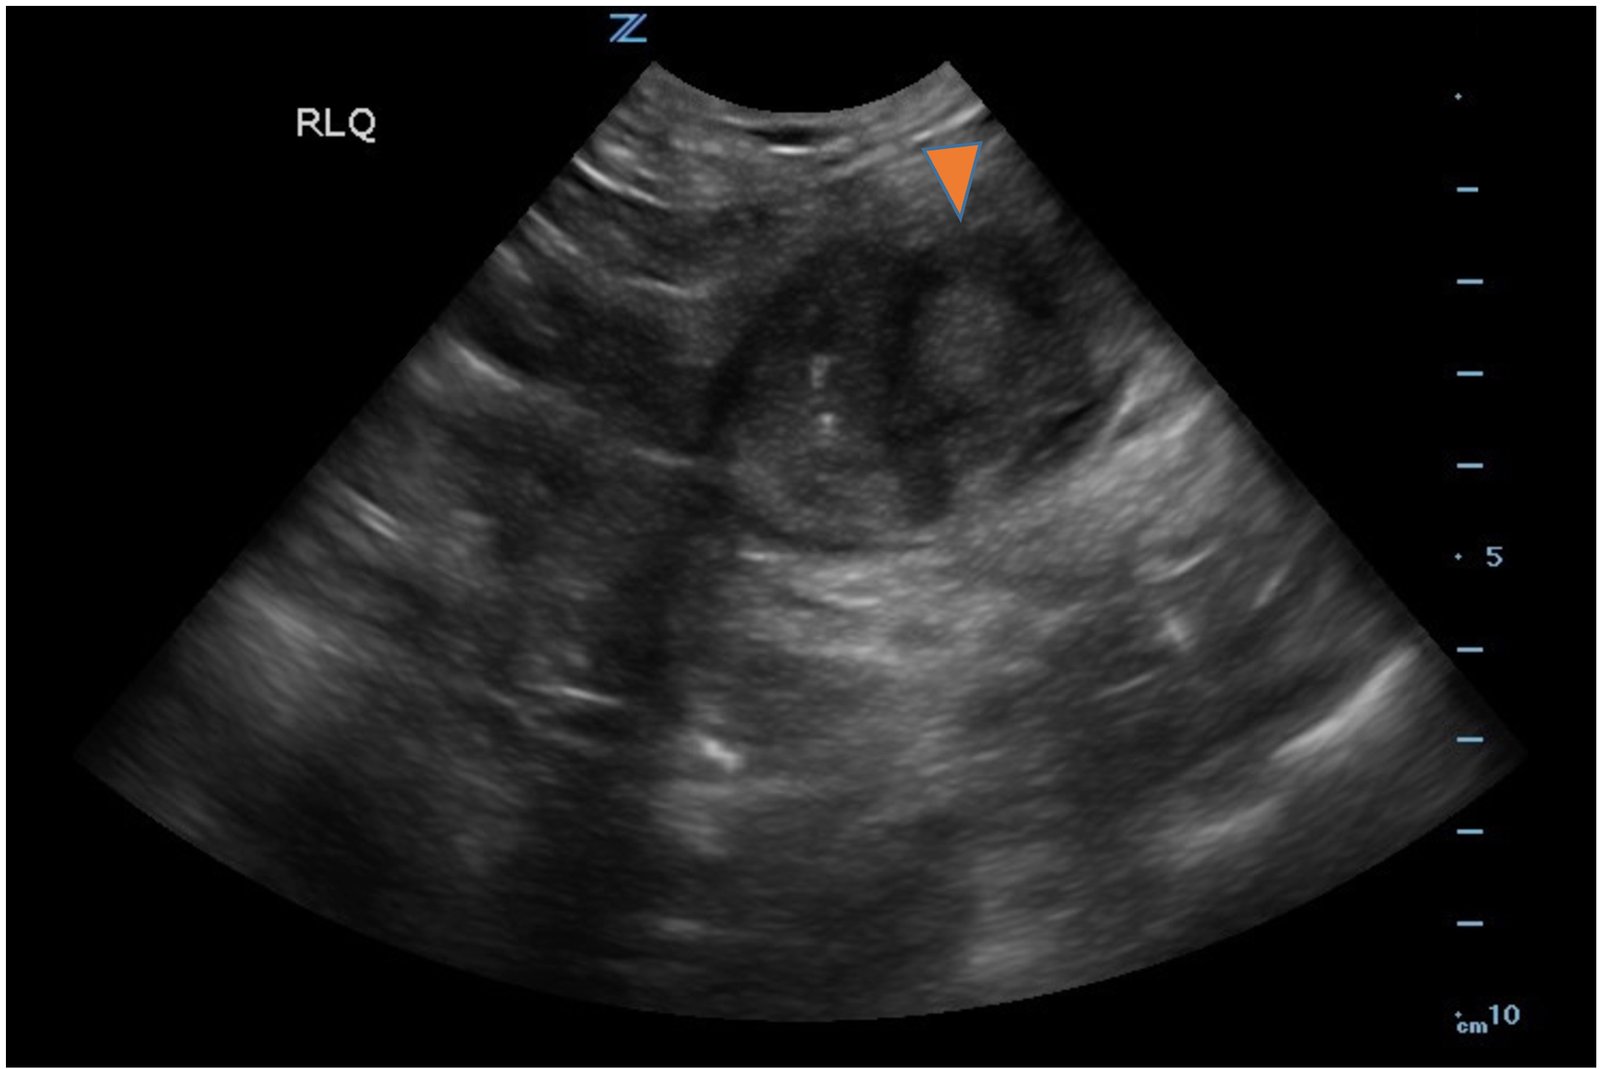

Small bowel diverticulitis is an uncommon subset of acute diverticulitis and can mimic many other intra-abdominal processes. As a result, imaging modalities such as ultrasound and computed tomography (CT) scan are especially important for timely recognition of diverticulitis and can expedite diagnosis and treatment and reduce complications. In the case described in this report, an 81-year-old male with history of esophageal cancer and recurrent diverticulitis with history of multiple bowel resections presented to the emergency department (ED) with right lower quadrant abdominal pain and constipation. Findings on ultrasound were suggestive of diverticulitis, and findings on CT of the abdomen and pelvis showed ileitis with phlegmon and micro-abscess suspicious for small bowel diverticulitis. ED providers should familiarize themselves with ultrasound findings of diverticulitis and be aware that diverticulitis can also present in the small bowel. Treatment of small bowel diverticulitis is similar to colonic diverticulitis.